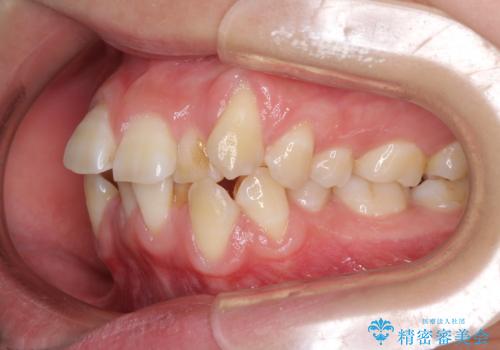

- 上下前歯の叢生と八重歯を気にして来院された患者様です。

前歯部叢生のスペースを獲得するため、上下顎左右小臼歯各1歯を抜歯することとしました。